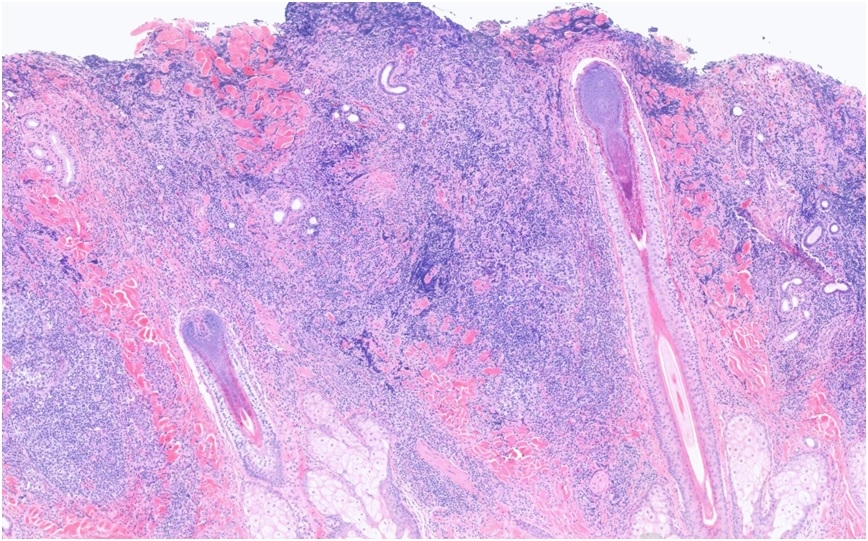

45 Year old male with forehead biopsy Itchy, raised plaque on on frontal hairline (no rash elsewhere). Red patches ?Seborrhoeic dermatitis (raised, erythematous)